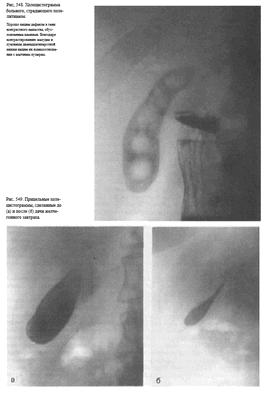

С помощью исследования кишечника специалист может обнаружить жидкости и газы, которые образуют «чаши» и «арки». На рентгенологическом снимке так называемые «чаши Клойбера» выглядят как газовые пузыри полукруглой формы. Картина чаши формируется, когда петля кишки содержит больше жидкости и небольшое количество газа, арки - наоборот. Чаша может трансформироваться в арку, а арка в чашу.

При кишечной непроходимости появляется сразу несколько чаш Клойбера, которые располагаются в центре брюшной полости, в районе петель тонкой кишки. На рентгенограмме это выглядит как вздутые участки кишки, заполненные жидкостью и газом.

Исследование пациента в вертикальном положении дает более четкую картинку, чем при боковом.

Современная рентгенодиагностика острой кишечной непроходимости основана, главным образом, на изучении скопления газов и жидкости в кишечнике. Они выглядят как светлые пятна на пленке. При такой ясной картине использование контраста излишне.